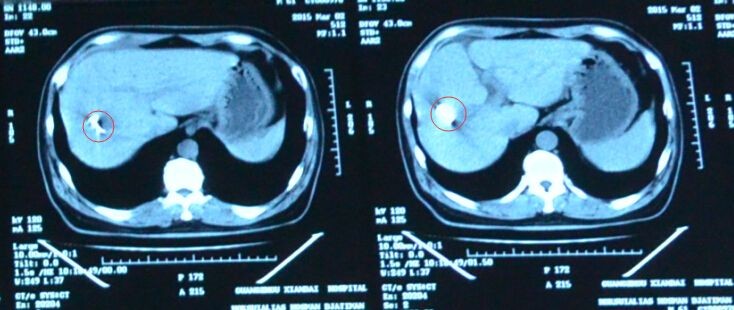

2014年9月,王祥瑞60歲,初次診斷出患有肝癌,當時腫瘤才2cm,他不願意手術,於是3個月後,肝臟的腫瘤已經長大到7cm,他來到廣州現代腫瘤醫院,確診為原發性肝癌肝內多發轉移(IV期)2015年12月,入院後,我們的MDT醫生團隊第一次為他進行了介入治療、冷凍治療。2015年1月,王祥瑞第二次入院,肝臟腫瘤已經明顯縮小和減少,於是,我們再針對剩餘的肝臟腫瘤植入40顆125I粒子。3月,當他再次來到醫院複查,我們看到他肝部的腫瘤已經消失了。(如下圖)

125I 粒子植入術定向爆破惡性腫瘤 ảnh 1 粒子植入。